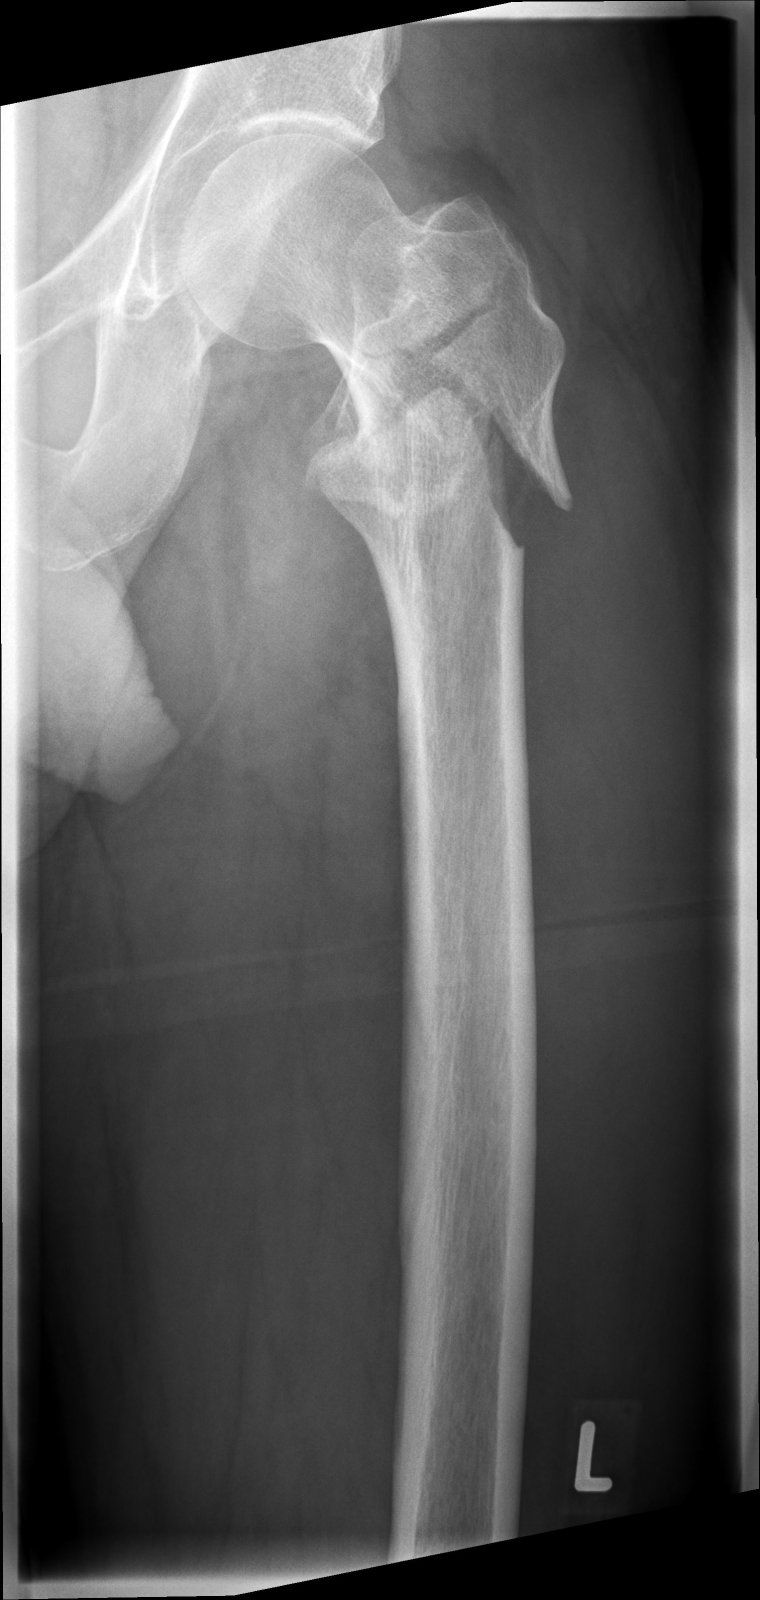

Habe heute mal die Röntgenbilder von der CD geholt.

Für nur über eine Kante gestolpert echt heftig. Habe gestern mit meiner Hausärztin gesprochen und direkt einen Cocktail aus Schmerzmittel, Vitamin D3 und Calcium verschrieben bekommen.